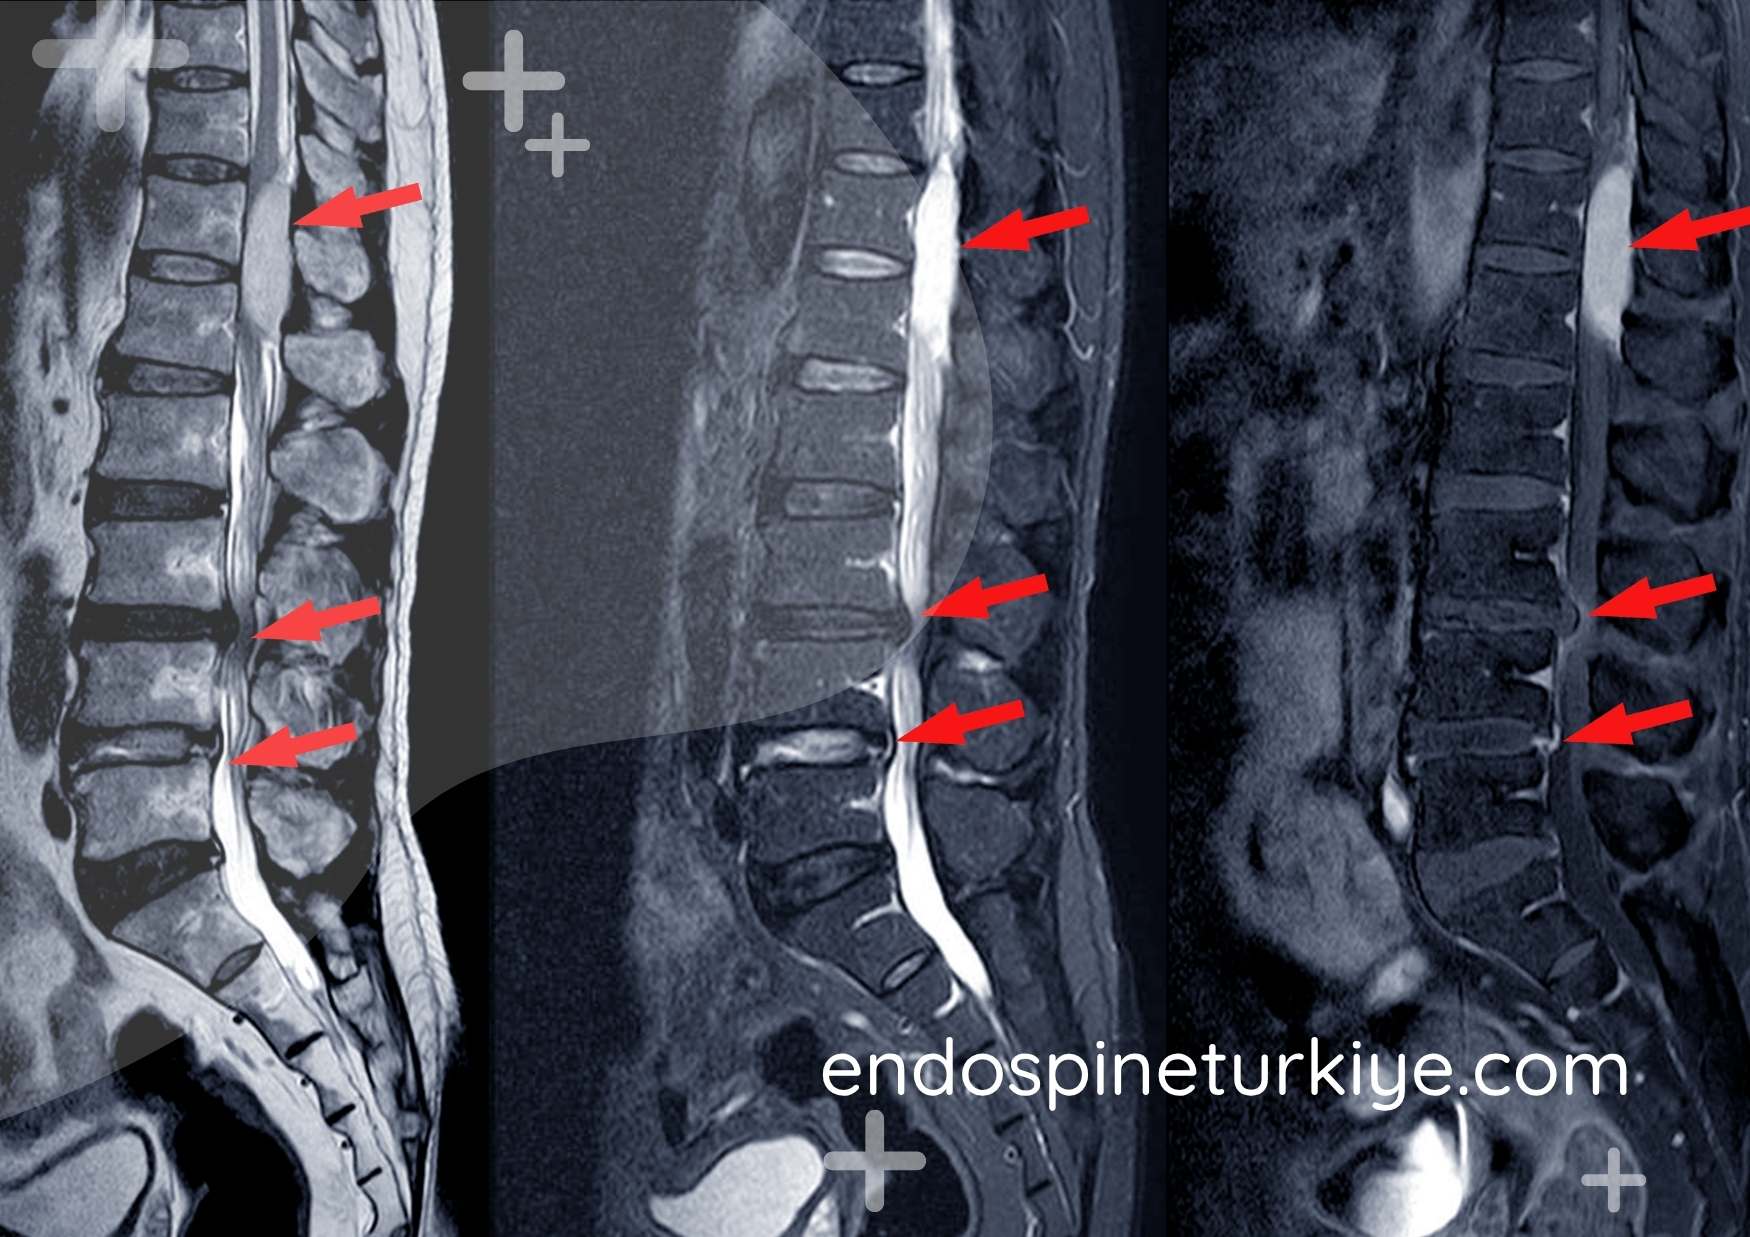

Dar kanal lomber MR görüntüsü - spinal stenoz teşhisi

Lomber MR görüntüsü - omurga kanalında daralma (spinal stenoz)